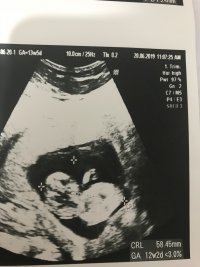

Ultrason sonucuna göre cinsiyet tahmini

Merhabalar gönderdiğim usg ye göre cinsiyet yorum yapar mısısnız

Selamlar malesef gönderdiğiniz resim sonuca ulaşmamız için yeteterli veri içermiyor. Lütfen aşağıdaki konumuzu inceleyerek ona göre resim atabilir misiniz ?